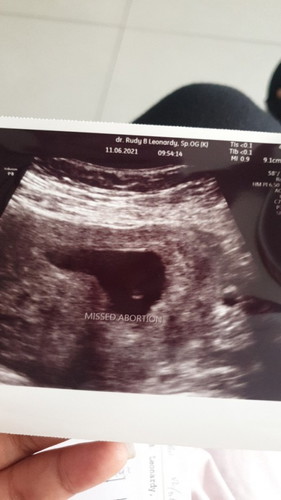

Jadi aku harusnya haid tanggal 3 januari. Tapi dri tanggal 1 itu mual muntah mulu. Trus ada flek pink tapi pagi aja munculnya. Trus malamnya flek coklat. Kaya awal mau haid gitu tapi sampe hari ini haidnya ga kunjung datang. Aku juga tiba2 sensitif sama bau2an. Pasti langsung Mual. Perutku nyeri kek mau haid. Aku sampe demam 2 hari, lemas dan loyo bgt. PD ku juga sering nyut2. Tanggal 4 aku ke dokter. Katanya rahim membesar. Sepertinya akan hamil. Tdi pagi aku TP tapi ( - ) baper aku tuh bun.. 😔😔😔😔 #pregnancy #Nanya #bantusharing #mommybuntu